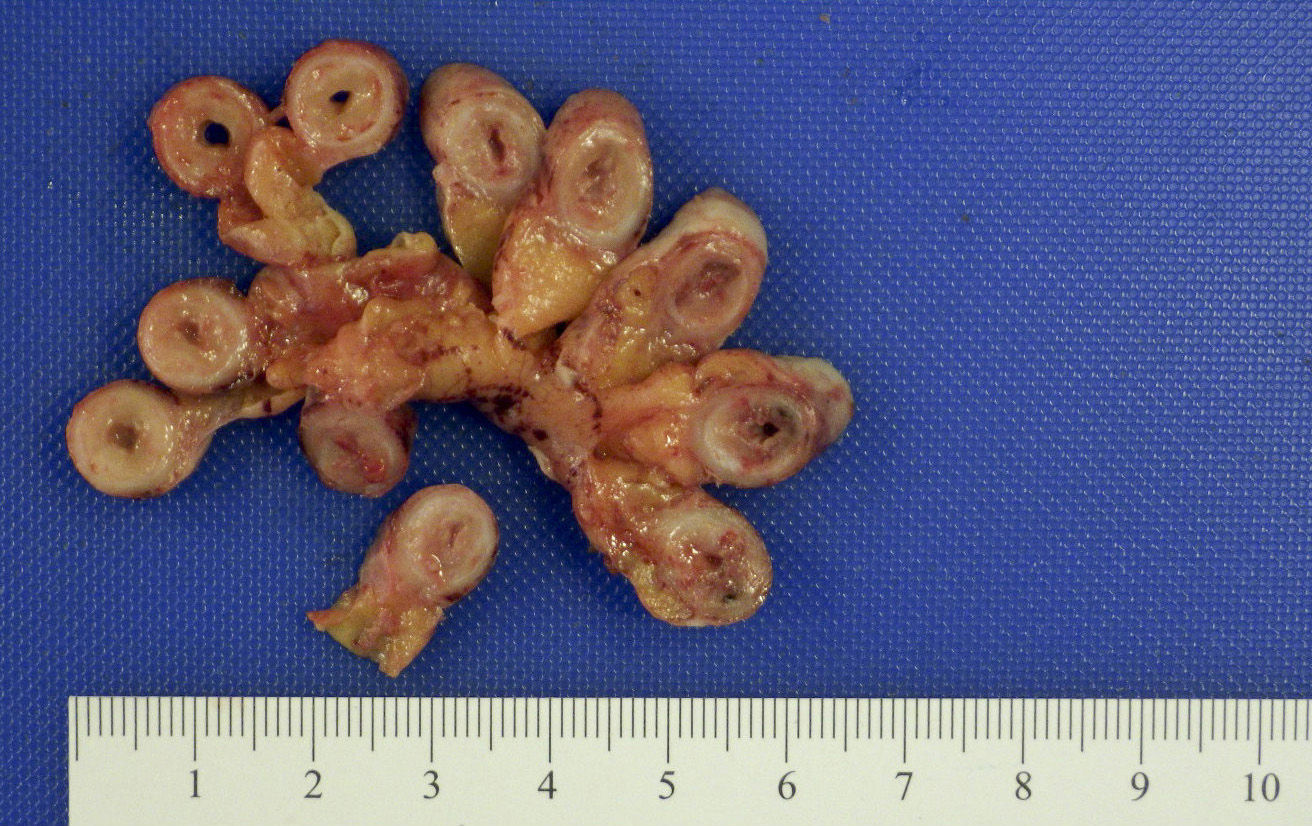

Gross description

- Gross and microscopic extent of inflammation may not correlate

- Inflammation may involve entire appendix or only a segment

- Appendix may appear grossly normal when inflammation is limited to the mucosa and submucosa

- Appendix appears swollen and erythematous when inflammation extends into the muscularis propria

- When the serosa is affected, a purulent exudate appears

- Cut surface may show hyperemia or intraluminal or intramural abscess

- Appendiceal wall may be completely necrotic in gangrenous appendicitis (J Pediatr Surg 2019;54:718)

- Perforation in severe cases

Gross images